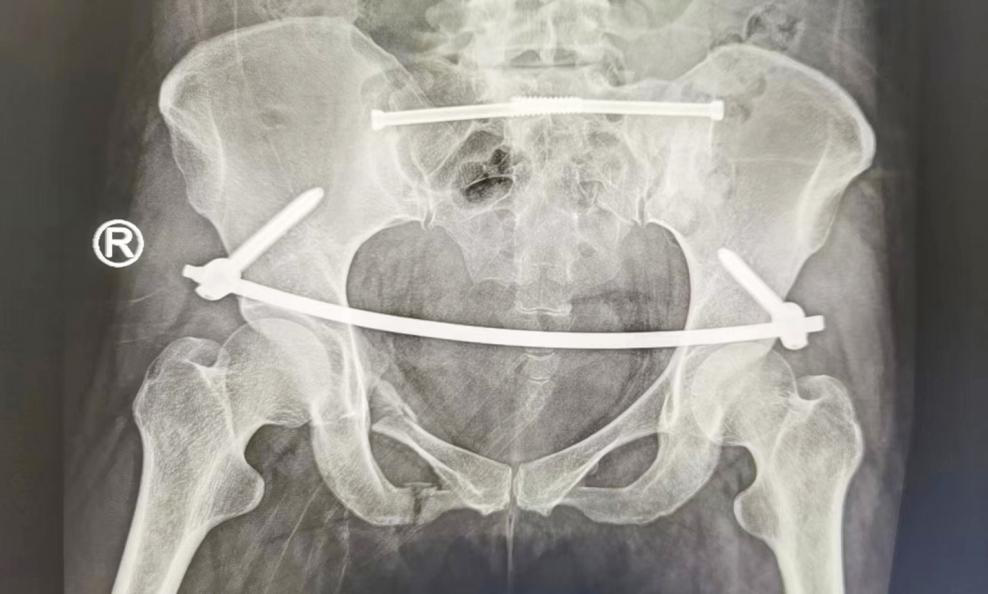

根据患者的伤情,创伤骨科任海东主任组织医生讨论手术方案,最终决定采用“机器人导航下多发性骨盆骨折复位内固定术”。骨盆骨折微创复位技术的优点是创伤小、费用低、恢复快、并发症少、固定可靠,能为病人快速康复奠定基础。

经充分术前准备并与患者沟通,任海东、信远、吴学业手术团队对患者实施了微创手术,仅通过几个1-3公分的小切口就完成了手术,出血量约50ml。

任主任表示,骨盆骨折微创技术克服了传统切开内固定创伤大、出血多、手术时间长的缺点,同时可以做到微创、美观的优点。术后患者可以自主洗澡、下蹲、跑跳,不影响日常生活。不夸张地说,骨盆微创技术,不仅造福广大骨盆骨折患者,还标志着我院在智慧骨科方面更进一步,跨入新的水平和阶段。